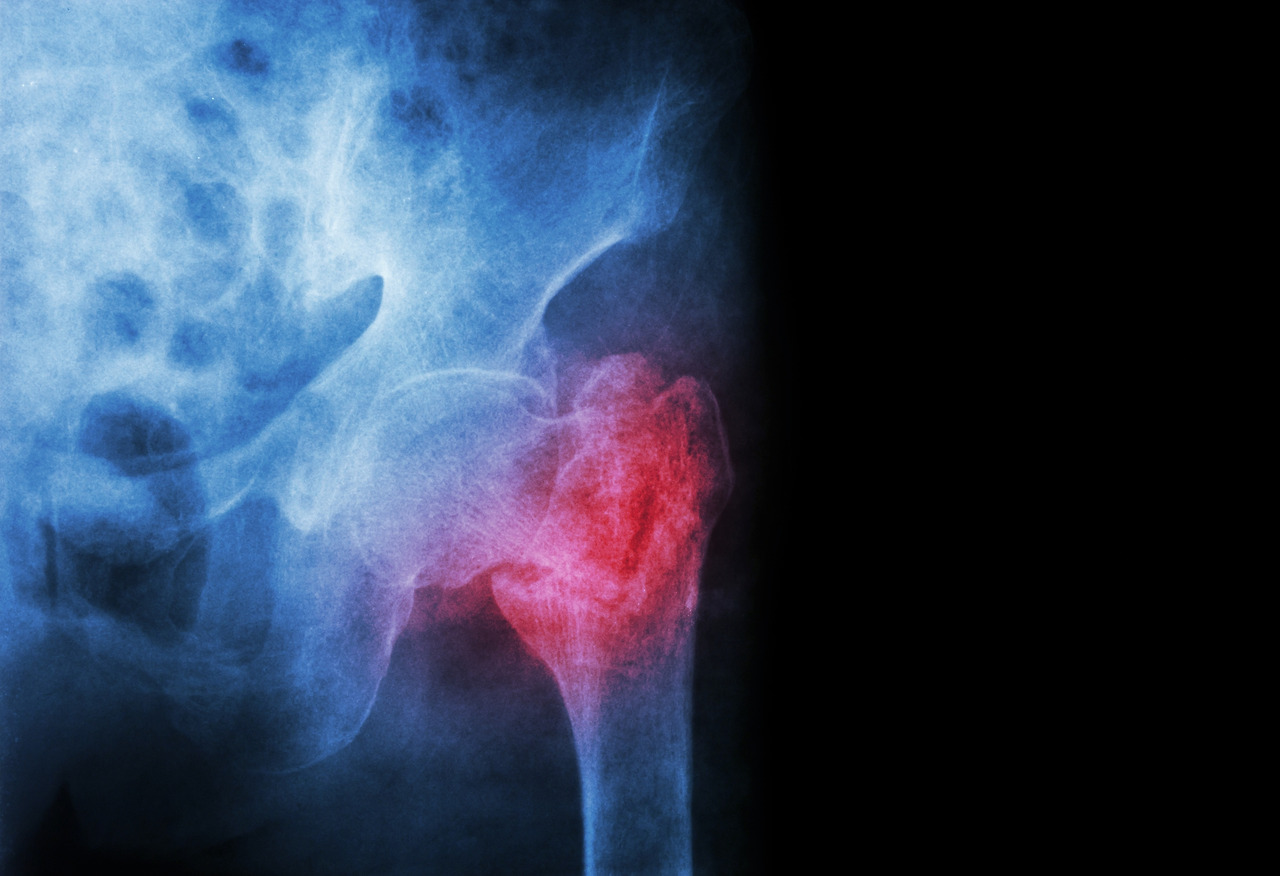

골절은 교통사고나 낙상과 같은 큰 사고가 아니라 생활 속에서 흔히 생기는 미끄러짐이나 부딪침으로도 생길 수 있어요. 이처럼 골절이 되면 일상생활에 여러 불편함이 생긴다는 것은 누구나 아는 사실이지요.

그러나 나이가 많은 노년층에서 고관절 골절이 생기면 사망까지도 이어질 수 있다는 사실을 아직 모르는 분들이 많답니다.

실제 노년층에서 유독 고관절 골절 환자가 많은 이유는 골다공증의 악화, 근육량의 감소, 척추 및 관절의 퇴행, 균형 감각 저하 등이 있습니다. 젊어서는 크게 무리가 가지 않는 충격에도 약해진 뼈가 쉽게 골절되는 것이지요.

가을을 만끽하기 위해 가을철 산행을 떠났지만 축축한 낙엽을 잘못 밟아 미끄러지거나 주저앉으면 고관절 골절이 생길 수 있습니다. 앞서 설명한 것처럼 나이가 들면 가벼운 외상만으로도 골절이 발생하기 쉬운데요. 아마 50대 이상부터 골다공증의 위험이 높으니 골절을 조심하라는 주변 이야기를 들어보신 적 있으실 거예요. 젊었을 때는 거뜬했던 충격에도 골절이 생기게 되는 것이지요.

더군다나 골다공증은 평소 그 위험성을 인지하지 못하는 경우가 많은데요. 완경이 된 50세 이후부터는 여성호르몬의 감소로 골다공증 위험성이 늘면서 매 10년마다 고관절 위험성도 2배 정도 높아집니다. 다시 말해, 자신도 모르는 사이에 뼈조직이 약해졌기 때문에 아주 위험한 고관절 골절의 위험이 점차 높아지는 것입니다.

특히, 고관절 골절이 생긴 후에 제때 치료를 받지 않으면 1년 내에 15~20% 정도가 사망한다고 합니다. 5년 이내 사망률은 45%나 된다니 정말 무섭네요. 고관절 환자의 일반인 대비 사망률은 남성 12배, 여성 11배로 매우 높으며 고관절 골절을 겪은 환자 중 많은 수가 이차성 고관절 골절이 발생합니다. 고관절 골절로 인해 거동이 불편해지면 욕창, 폐렴, 심장질환 등 치명적인 합병증으로 이어지는 경우가 많아요.